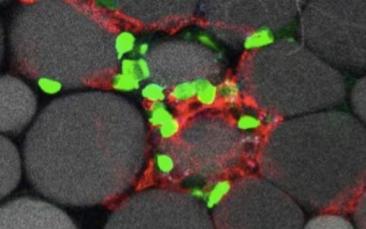

Lymphocytes versus hepatitis B virus: caught in action

For the first time ever, two ERC grantees, Prof. Luca G. Guidotti and Dr Matteo Iannacone, have observed in vivo how specific white blood cells, so-called cytotoxic T lymphocytes, identify, target and attack liver cells that are infected with the…For the first time ever, two ERC grantees, Prof. Luca G. Guidotti and Dr Matteo Iannacone, have observed in vivo how specific white blood cells, so-called cytotoxic T lymphocytes,…For the first time ever, two ERC grantees, Prof. Luca G. Guidotti and Dr Matteo Iannacone, have observed in vivo how specific white blood cells, so…For the first time ever, two ERC grantees, Prof. Luca G. Guidotti and Dr Matteo Iannacone, have observed in vivo how specific white blood cells, so-called cytotoxic T…For the first time ever, two ERC grantees, Prof. Luca G. Guidotti and Dr Matteo Iannacone, have observed in vivo how… -